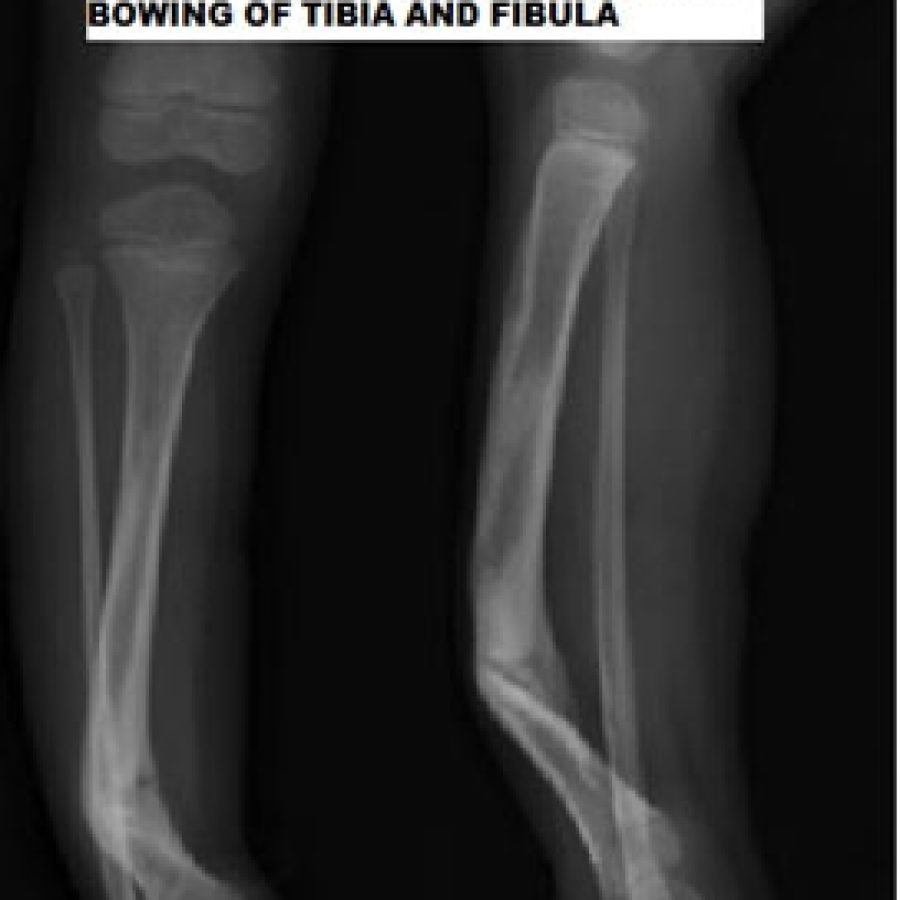

CONGENITAL POSTEROMEDIAL BOWING

Posteromedial bowing is a benign clinical condition with a good natural history. It is mostly due to the intrauterine positioning of the leg. It is most often associated with calcaneovalgus foot. It spontaneously corrects by the age of 5-7 years. If there is more than 3-4 cm of shortening, then surgical intervention is necessary to equalize the limb length.

Most often than not, this should not be confused with anterolateral bowing of the leg, which is almost always pathological. Anterolateral bowing is mostly because of congenital pseudarthrosis of the tibia. Congenital Pseudarthrosis of tibia and fibula is one of the most challenging surgical problems in pediatric orthopedic surgery, and it is important to distinguish from benign posteromedial bowing of the tibia.

When to Refer

It is important to refer all bowing of the leg to the pediatric orthopedic surgeon as sometimes it is difficult to differentiate the two disorders. If one is very sure about the Posteromedial bowing of the leg, then one can wait for 2-3 years with reassurance to the family